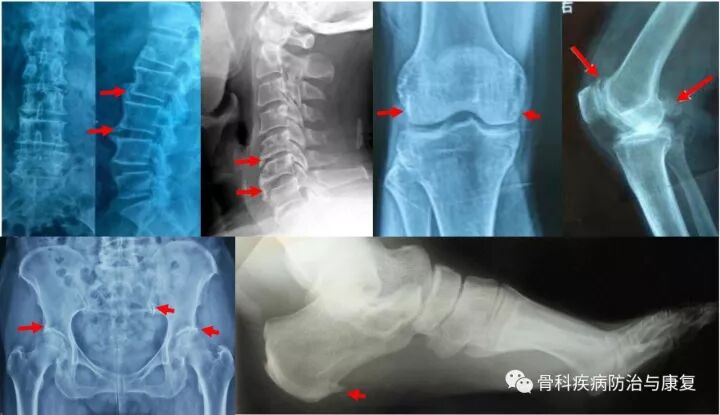

图1 常见部位骨质增生X片

骨质增生最常见的部位是人体负重的大关节,尤其膝关节,其次是人体脊柱关节,尤其是颈腰椎,除此之外,还有负重的跟骨骨刺也非常常见。这些关节要么是活动度很大,要么就是负重很多的部位,也就是应力集中区域。因此这些区域最常发生骨质增生,尽管有那么多人检查出有骨刺,但并非所有长骨刺的人都有临床症状,且临床症状严重程度也与骨刺的大小、多少不一定呈正比,通常也都不需要手术治疗。